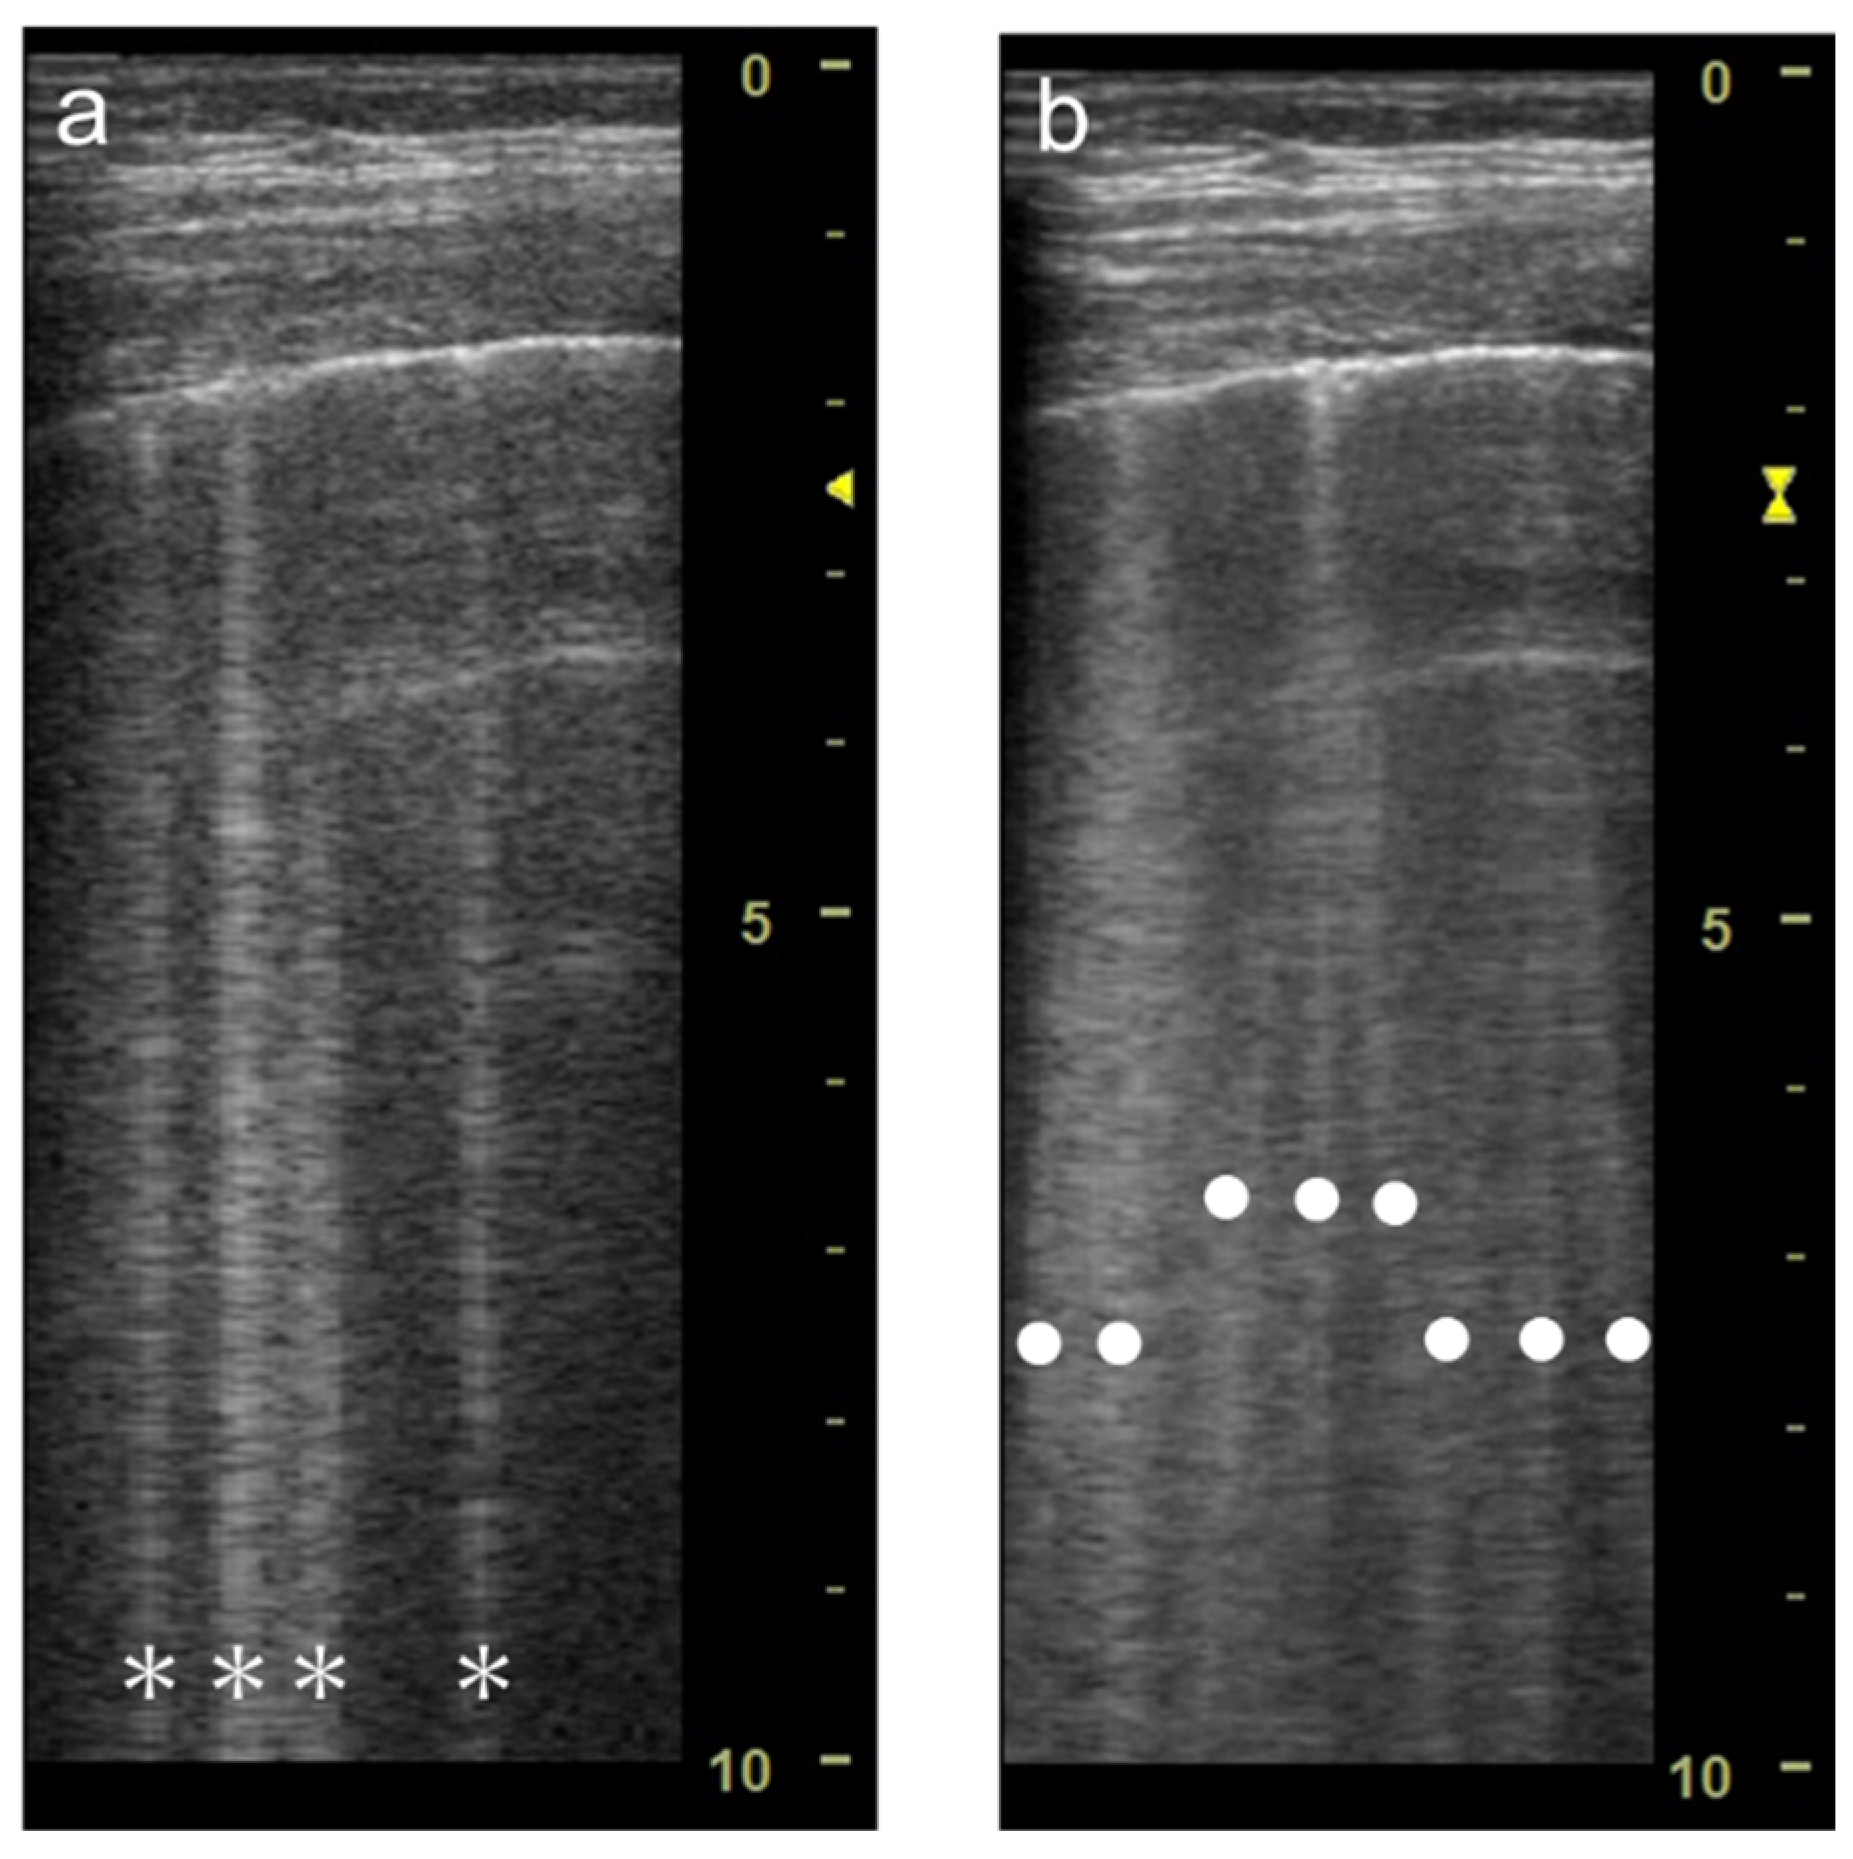

3.1. Spatial Compound Imaging

3.2. Focal Point